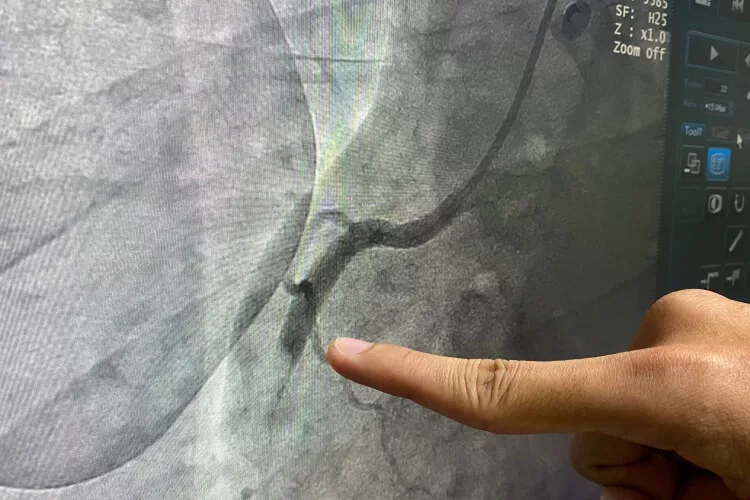

Ilustrační obrázek

Zdroj: Shutterstock